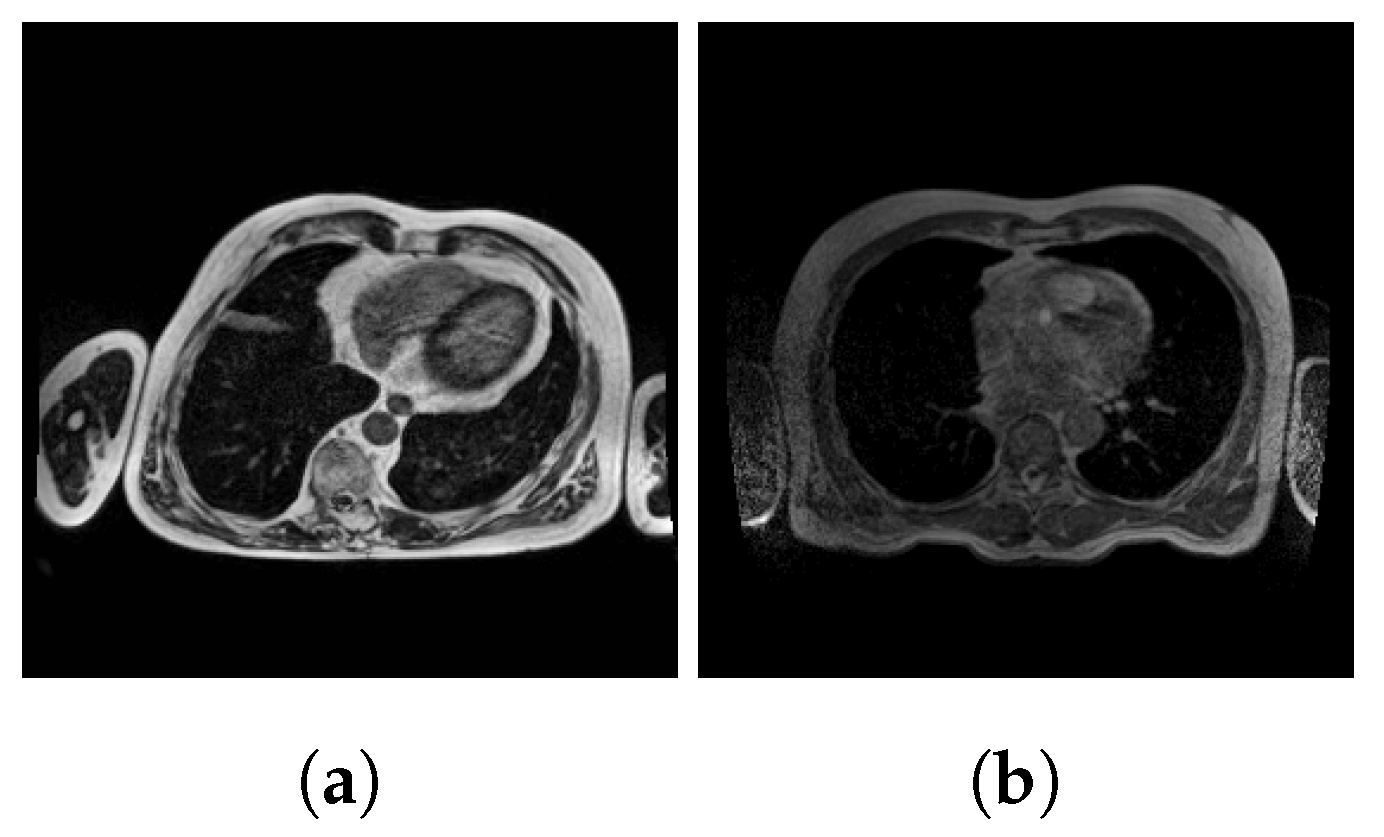

2.2. Preprocessing